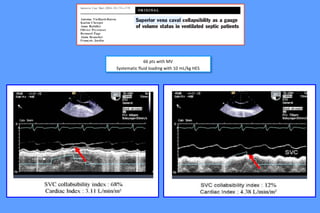

66 pts with MV

Systematic fluid loading with 10 mL/kg HES

66 pts withMV Systematic fluid loading with 10 mL/kg HES